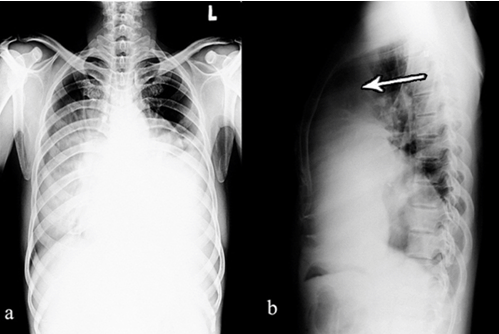

Plain and contrast computed tomography (CT) scan of chest showed a large heterogeneous mass in anterior mediastinum (Figure 2a). The mass lesion was seen extending into anterior half of right hemithorax, from apex to diaphragm with partial collapse of right lung (Figure 2c). On left side, the mass is occupying most of the hemithorax, causing collapse of lower lobe and lingular segments of left lung (Figure 2c).

The mass showed predominantly fatty component with interspersed soft tissue component and few cystic areas and a dense nodular calcifications (Figure 2c). There is mild heterogeneous enhancement of the soft tissue component on IV contrast administration (Figure 2b, 2d).

Figure 2: Axial computer tomography scan images of chest (a) plain and (b) contrast at the level of arch of aorta showing heterogeneous mass with fat (*) and soft tissue (arrow head) attenuation in anterior mediastinum with mild enhancement of solid component on contrast administration. Axial CT images of chest (c) plain and (d) contrast at the level of ventricles: showing heterogeneous mass with solid component (arrow head), fat (*), cystic areas (solid arrow) and nodular calcification (open arrow), occupying anterior half of right hemithorax and complete left hemithorax.